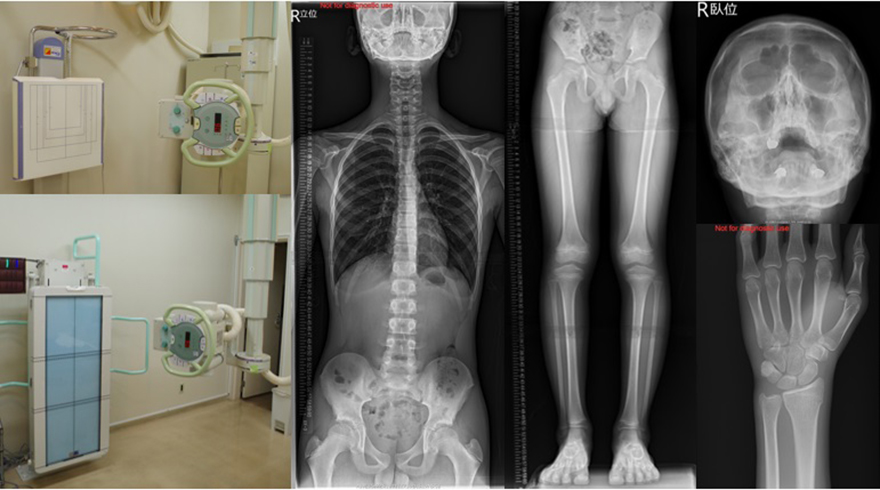

一般撮影

2室

- 島津製作所 Radiotex 2台

- Canon DRシステム 2台(長尺撮影台 1台)

健康診断の胸部の撮影から、各部位の骨の撮影など全身の撮影を行います。

当院ではDRシステムとしてFPDを導入し低線量での撮影が可能となり、

被ばく低減に努めています。